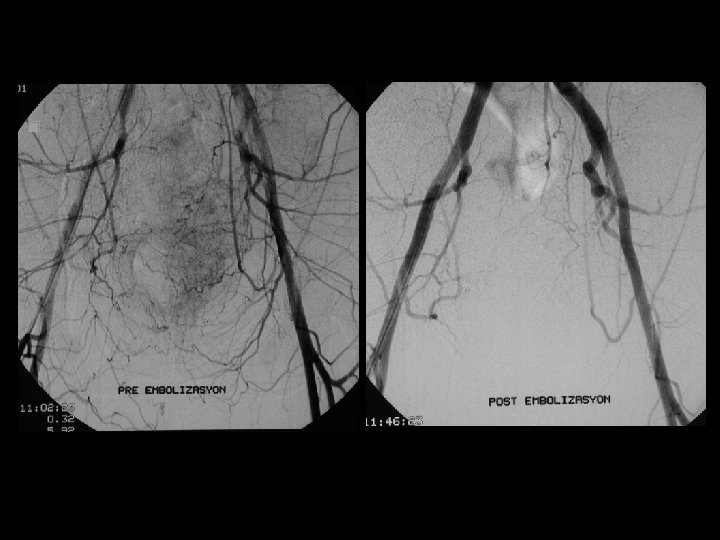

Pre emb. Post emb.

HCC; kemoembolizasyon